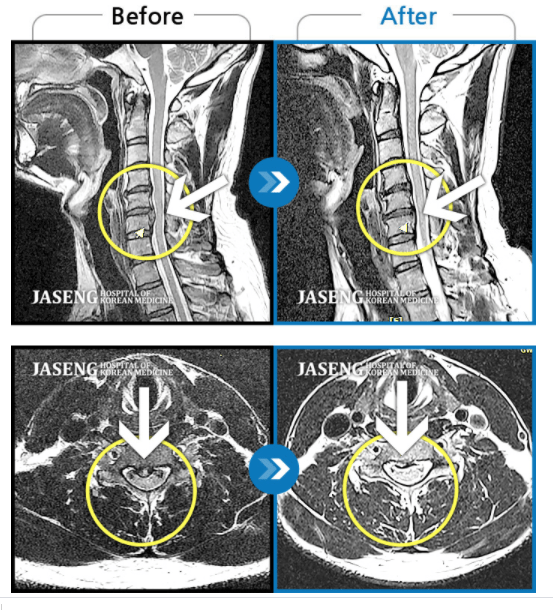

МРТ до и после. Грыжа в шее рассосалась без операции!